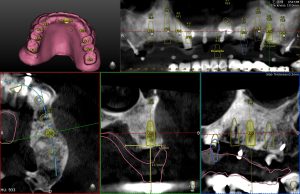

- 沒有詳盡的客製化治療計畫:在全口重建 All on 4/6/X 每根支柱植體都至關重要,除了需要品質良好的骨頭外,植體角度、位置、寬度長度的選擇都會直接影響 All on 4/6/X 的成功率。在選擇植牙位置的部分,郭光哲醫師選用全數位化假牙規劃,利用電腦模擬未來理想假牙位置,再根據理想假牙位置規劃植牙位置。依據病患狀況客製化設計植體所需顆數,最後再搭配 Navident 4D 導航精準植入規劃植體,同時保障手術過程中的安全。市面上沒有完善手術規劃,沒有搭配導板導航的植牙,只靠手術醫師眼睛判斷的 All on 4/6/X ,最終都可能迎來高失敗率,或無法長久使用。

- 術前評估:初診時,郭光哲醫師會先了解患者的身體狀況以及有無任何手術禁忌症。確認身體狀況許可後為患者拍攝全口 X 光和電腦斷層影像(CBCT),接著會了解患者的需求,擬定專屬的治療計畫,並告知詳細的療程費用、保固及注意事項。

- 資料搜集:術前一週,郭光哲醫師會為患者進行 3D 數位口腔掃描及拍攝口內外照片。根據醫師所制定的治療計畫,醫師和技師將共同討論並依照患者的五官特徵,客製化手術當天所需的臨時假牙

- 植牙手術:手術日早上,郭光哲醫師會依照治療計畫在每顎植入植體,植牙過程在舒眠麻醉下執行,並由專業的麻醉科醫師協助監控,讓患者一覺起來輕鬆完成手術,毫無壓力。為了追求完美,郭光哲醫師在每個 All on X 手術中都會搭配最新 Navident 4 (AR擴增實境數位導航),完美執行精準與安全。手術完成後,需要等待2到6個月,讓植體與骨頭完全密合。接著郭光哲醫師會開始製作正式假牙讓患者試戴,並根據病人的反饋進行調整,最後製作出兼具美觀與功能的正式假牙。

搭配數位導航:一日全口重建 All on X 為複雜牙科手術,搭配 Navident 4D 數位導航可以精準避開重要的神經、血管、鼻竇。在精準植牙同時保障病患安全。